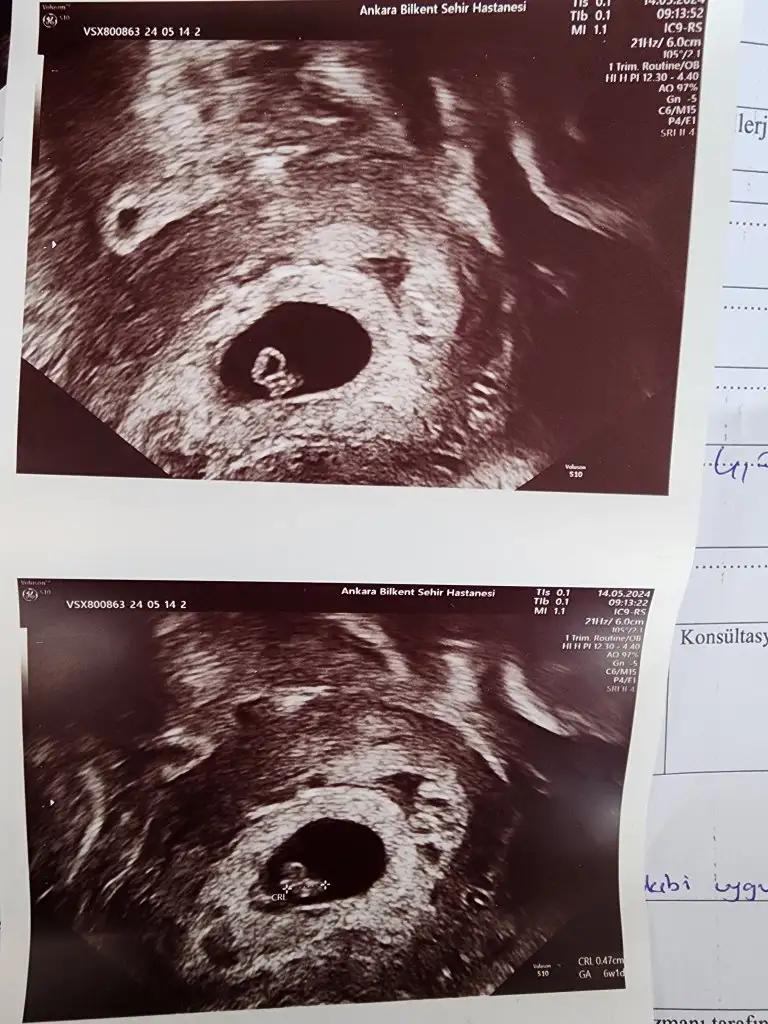

Meraba hanımlar bende bugün gittim doktora 7 haftalık hamileyim karından usg ile görüntümü atıyorum tahminde bulunurmusunuz

Eklentiler

• IMG_2752.webp

25,9 KB · Görüntüleme: 91